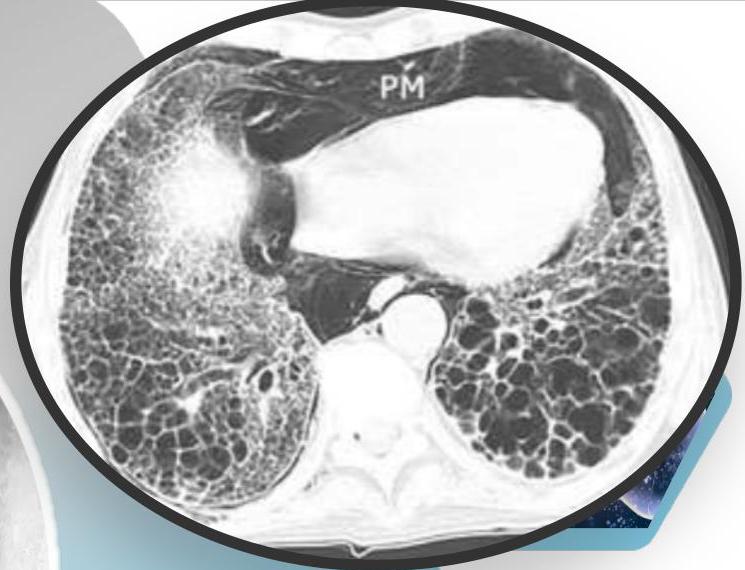

CT Scan Findings

Cylindrical

Saccular/Varicoid

Cystic